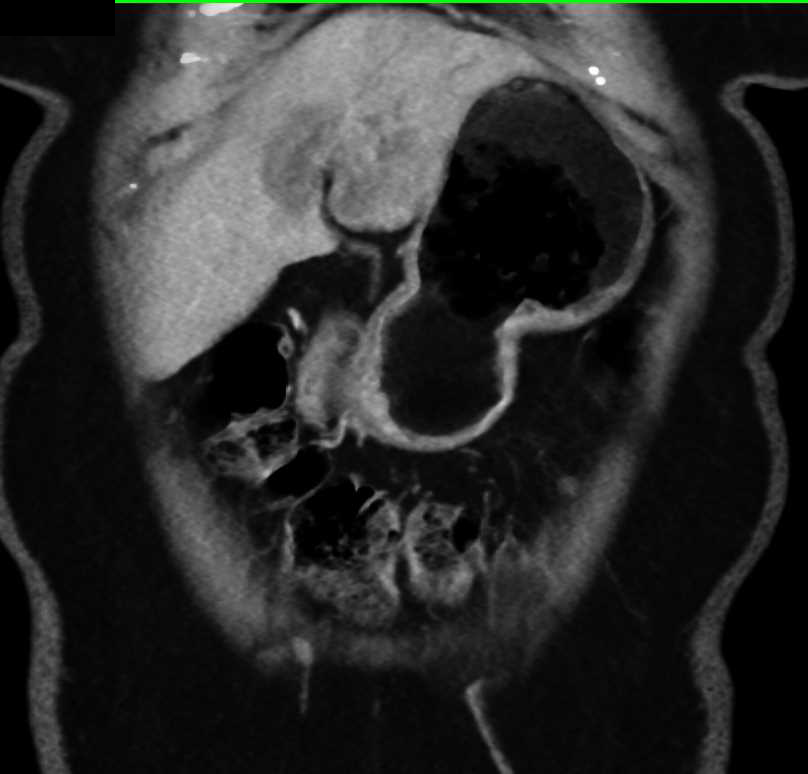

CT scan slices showing extensive metastatic liver cancer Stock Photo …

CT scan showing 4 measurable liver lesions with image markup of longest …

CT scan showing cancer of the liver – Stock Image – M134/0245 – Science …